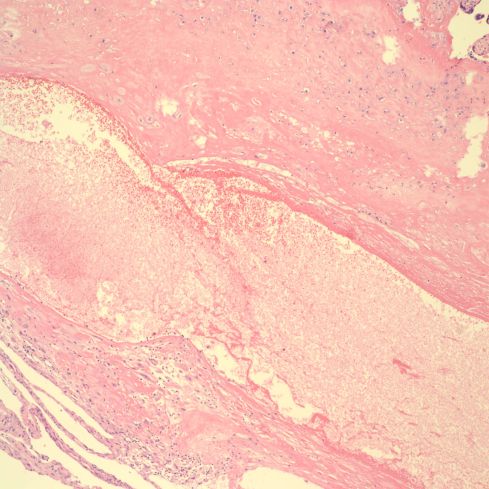

In older infarctions, the spiral arteries may demonstrate sparse red cells with loss of hemoglobin consistent with vascular stasis or with partial mural thrombi (Figs 25-29).

Fig 25: The infarction shows the compacted pale villi in the lower portion of the image. Above the infarction a complex spiral artery profile shows lumen empty except for some faded blood cells. (H&E, 2x)

Fig 26: This is another infarction, oriented above the base of the placenta, which runs across the lower left corner of the image. In the lower left of this diagonal can be seen a dilated spiral artery that appears empty except for faded blood cells. There is no thrombus at this level of the superficial decidua, although the infarction is evidence of vascular occlusion in the spiral artery. (H&E, 2x)

Fig 27: This is a higher power image of the above artery showing the thin wall without a definable media. (H&E, 10x)

Fig 28: This is similar to the above two cases. The infarction to the left with the base of the placenta shows above it in the image. The base demonstrates a long, complex set of cross sections of a spiral artery showing old, pale red cells. (H&E, 2x)

Fig 29: The vascular profile in the right corner of Fig 28 demonstrates some non-occlusive mural thrombus in this higher power image. (H&E,10x)

The implication is that the occlusion of the vessel, mostly likely from thrombus, occurred proximal to the portion of spiral artery in the most superficial dedicua. In retroplacental hematoma, vessels may demonstrate rupture and hemorrhage into the underlying decidua. In infarction hematoma, a spiral artery may appear to rupture into the intervillous space. In most cases of these complications, no spiral artery is identified, likely because it has not been sampled, or is no longer attached to the placenta.